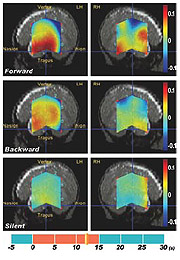

光トポグラフィの最新の成果として,新生児の言語機能の計測結果が2003年9月に発表され,世界的に注目を集めています(イタリア高等研究所のJ.Mehler教授との共同研究)。これは,生後2日から5日の新生児に,(1)母国語の話を聞かせる,(2)その話の逆回しの音を聞かせる,(3)何も音の刺激を与えない,という三とおりの状況で脳血流の変化を計測した実験でした。その結果,普通に順回しで話を聞かせたときに,明らかな反応が左側頭葉で観察されました。生後まもない新生児が,すでに左側頭葉の言語野で言語音を処理していることが世界で初めて明らかになったものです。